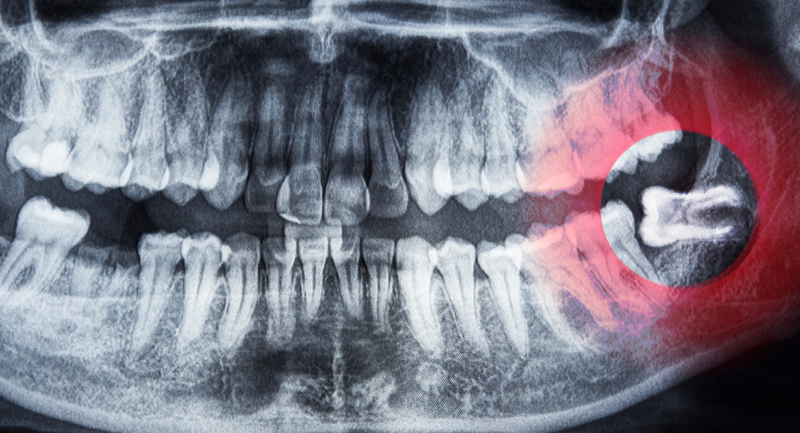

Research conducted into growth and development of children has made growth modification treatments available too. Now there is much less need for the extraction of teeth, as growth patterns can be identified through early assessments, x-rays, and 3D models.